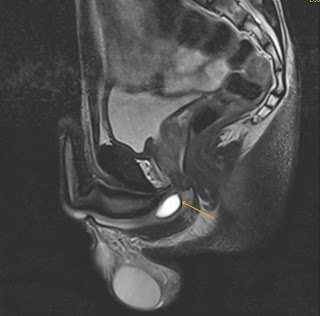

It usually only occurs if you already have nodules in your thyroid gland. Normal Cowper glands and ducts are imperceptible at imaging.

Talk to a doctor now . sunglasses to protect the eyes against bright lights, damage to the thyroid gland, such as a punch to the throat, a very rapid heartbeat (over 140 beats a minute), fever (a temperature higher than 38C/100.4F), jaundice a yellow tinge to your skin and eyes, hallucinations seeing or hearing things that are not real. In some cases, tests may show you havenormal thyroid hormone levels, but low or suppressed levels of TSH. Answer: Not necessarily. This is inflammation of the bulbourethral glands and presents with fever, malaise, and in some cases severe perineal pain. Unable to process the form. (a curve to the penis).